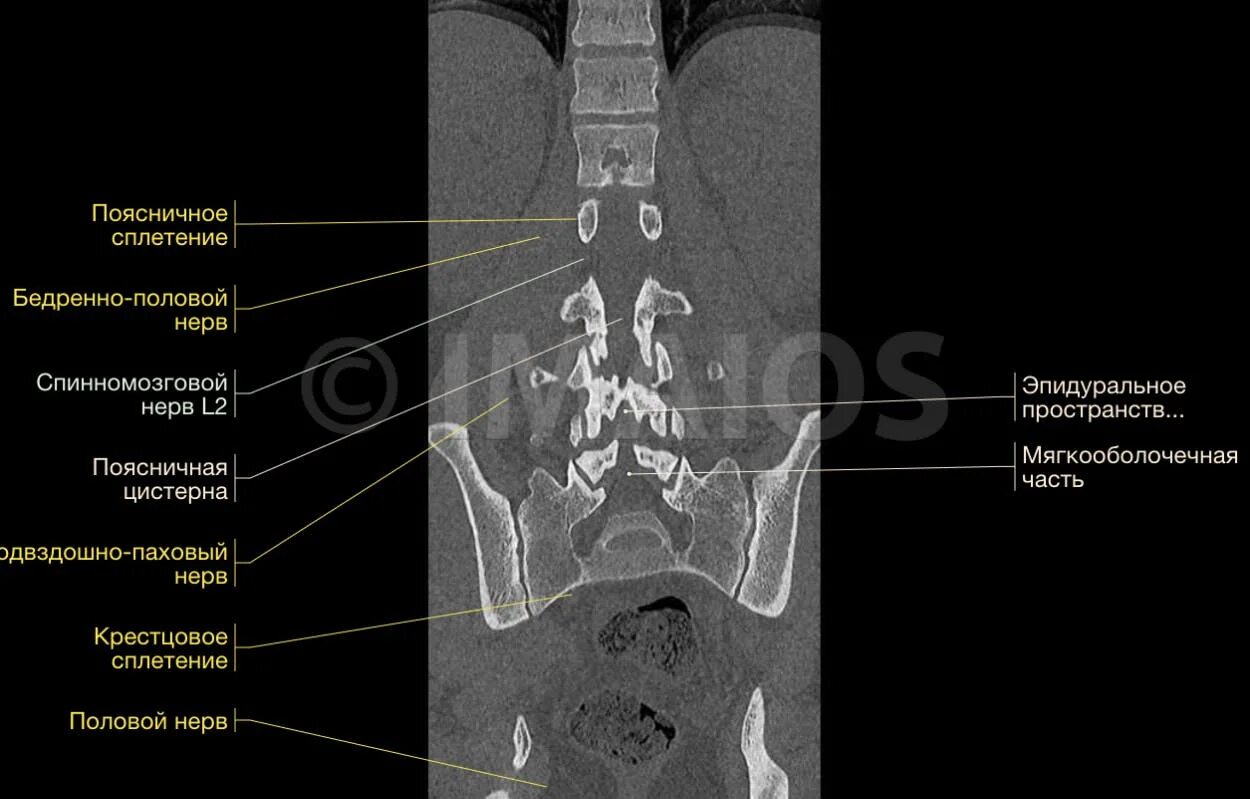

Как делают кт пояснично крестцового отдела